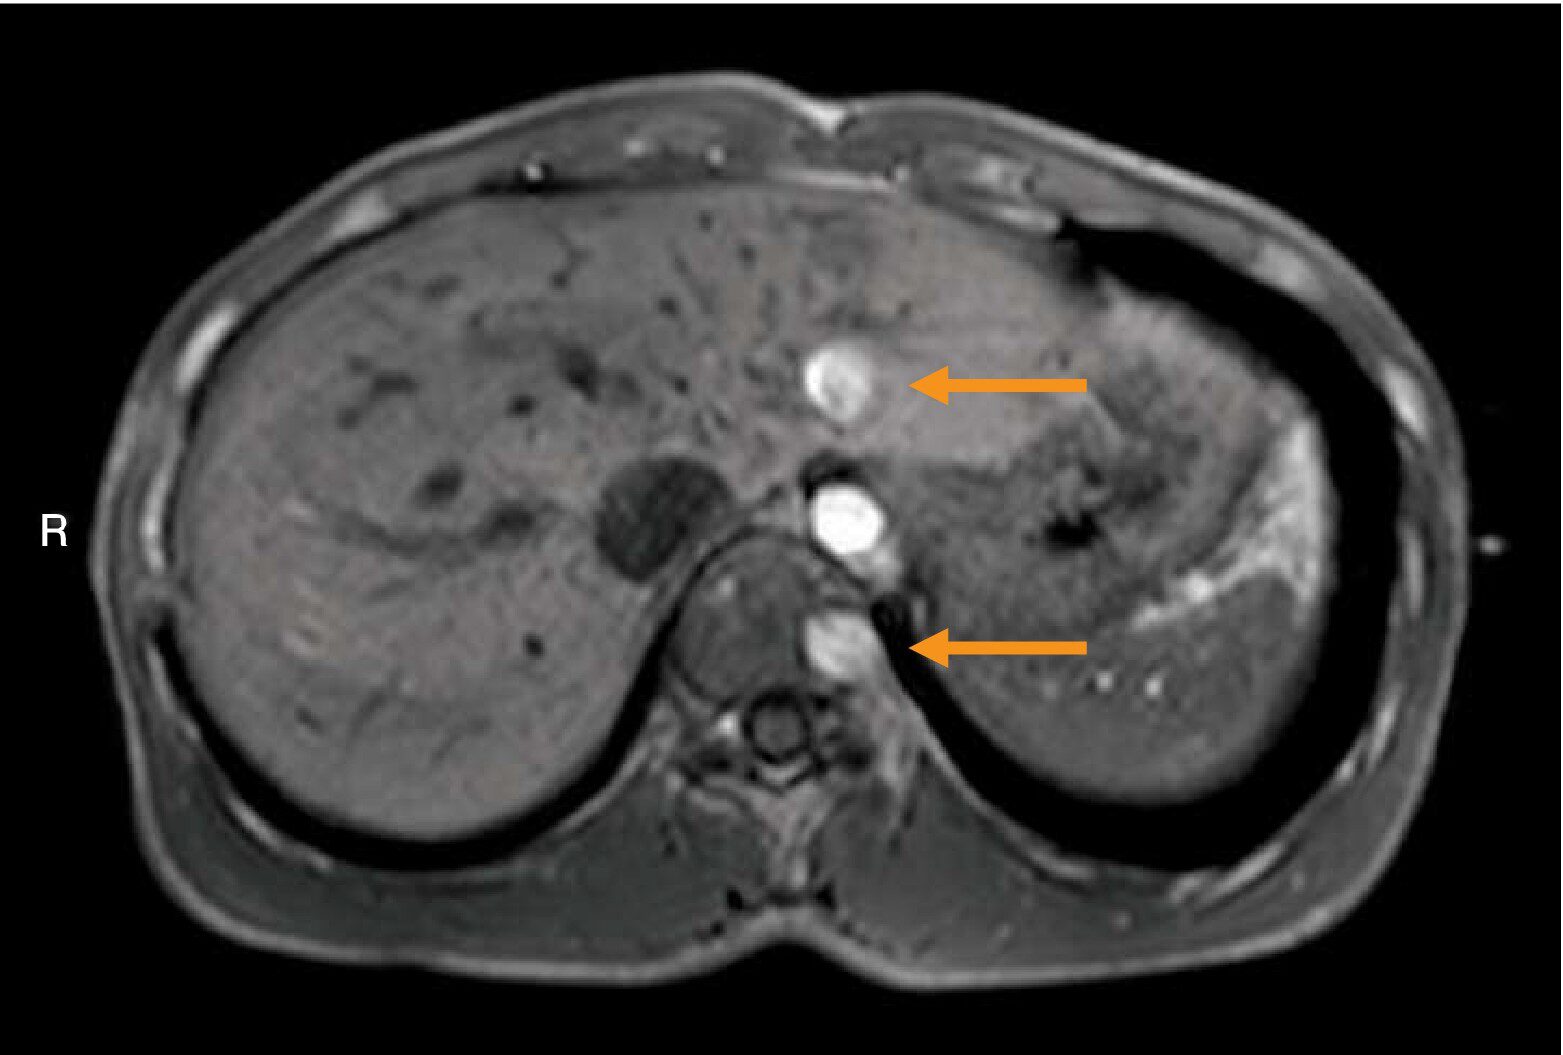

腹部MRIのT1強調像(別冊No.5)を別に示す。矢印で示すのはどれか。